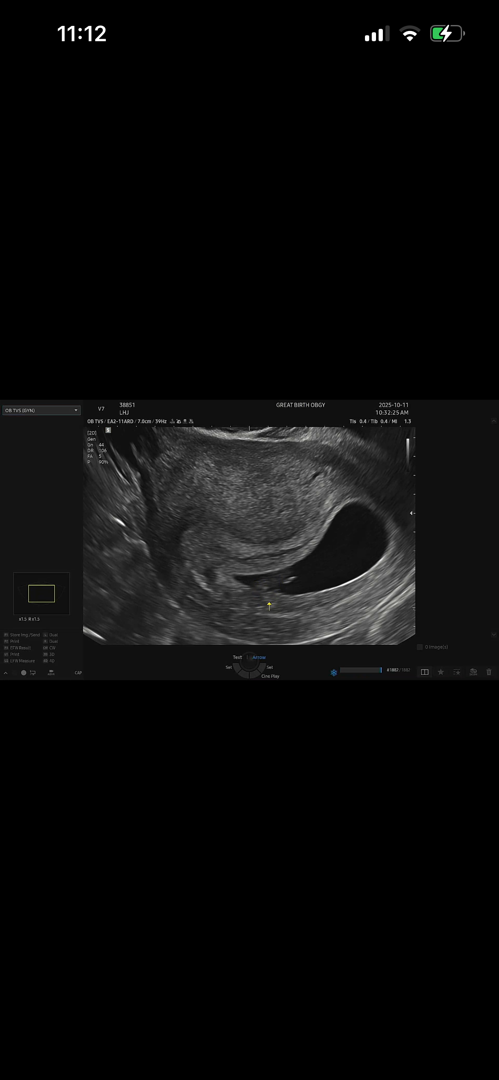

안녕하세요 7주1일에 초음파보고 아기심장소리 147bpm에 1.07cm 동그란난황까지 보고 왔습니다 근데 아기집모양이 말풍선모양처럼 끝이 뾰족해요.. 의사선생님은 모양애대해선 아무말씀 안하셨고 아기 잘크고있다고 2주뒤에 보자고하셨는데, 이리저리 글보니까 아기집모양에 대해서 동그랗지않으면 유산기가 있는거라고해서요..ㅜㅜ 아기집모양이 이렇게보였던분 있으신가요..

저도 완전 말풍선 모양이였어요. 일주일 지나니 동그래지더라구여 ㅎㅎ 걱정마세요!!

저도 6주 촘파 봤을때 이랬는데 지금 10주차고 아기집 문제없이 잘 커졌어요! 의사선생님이 아무말없었으면 괜찮아요